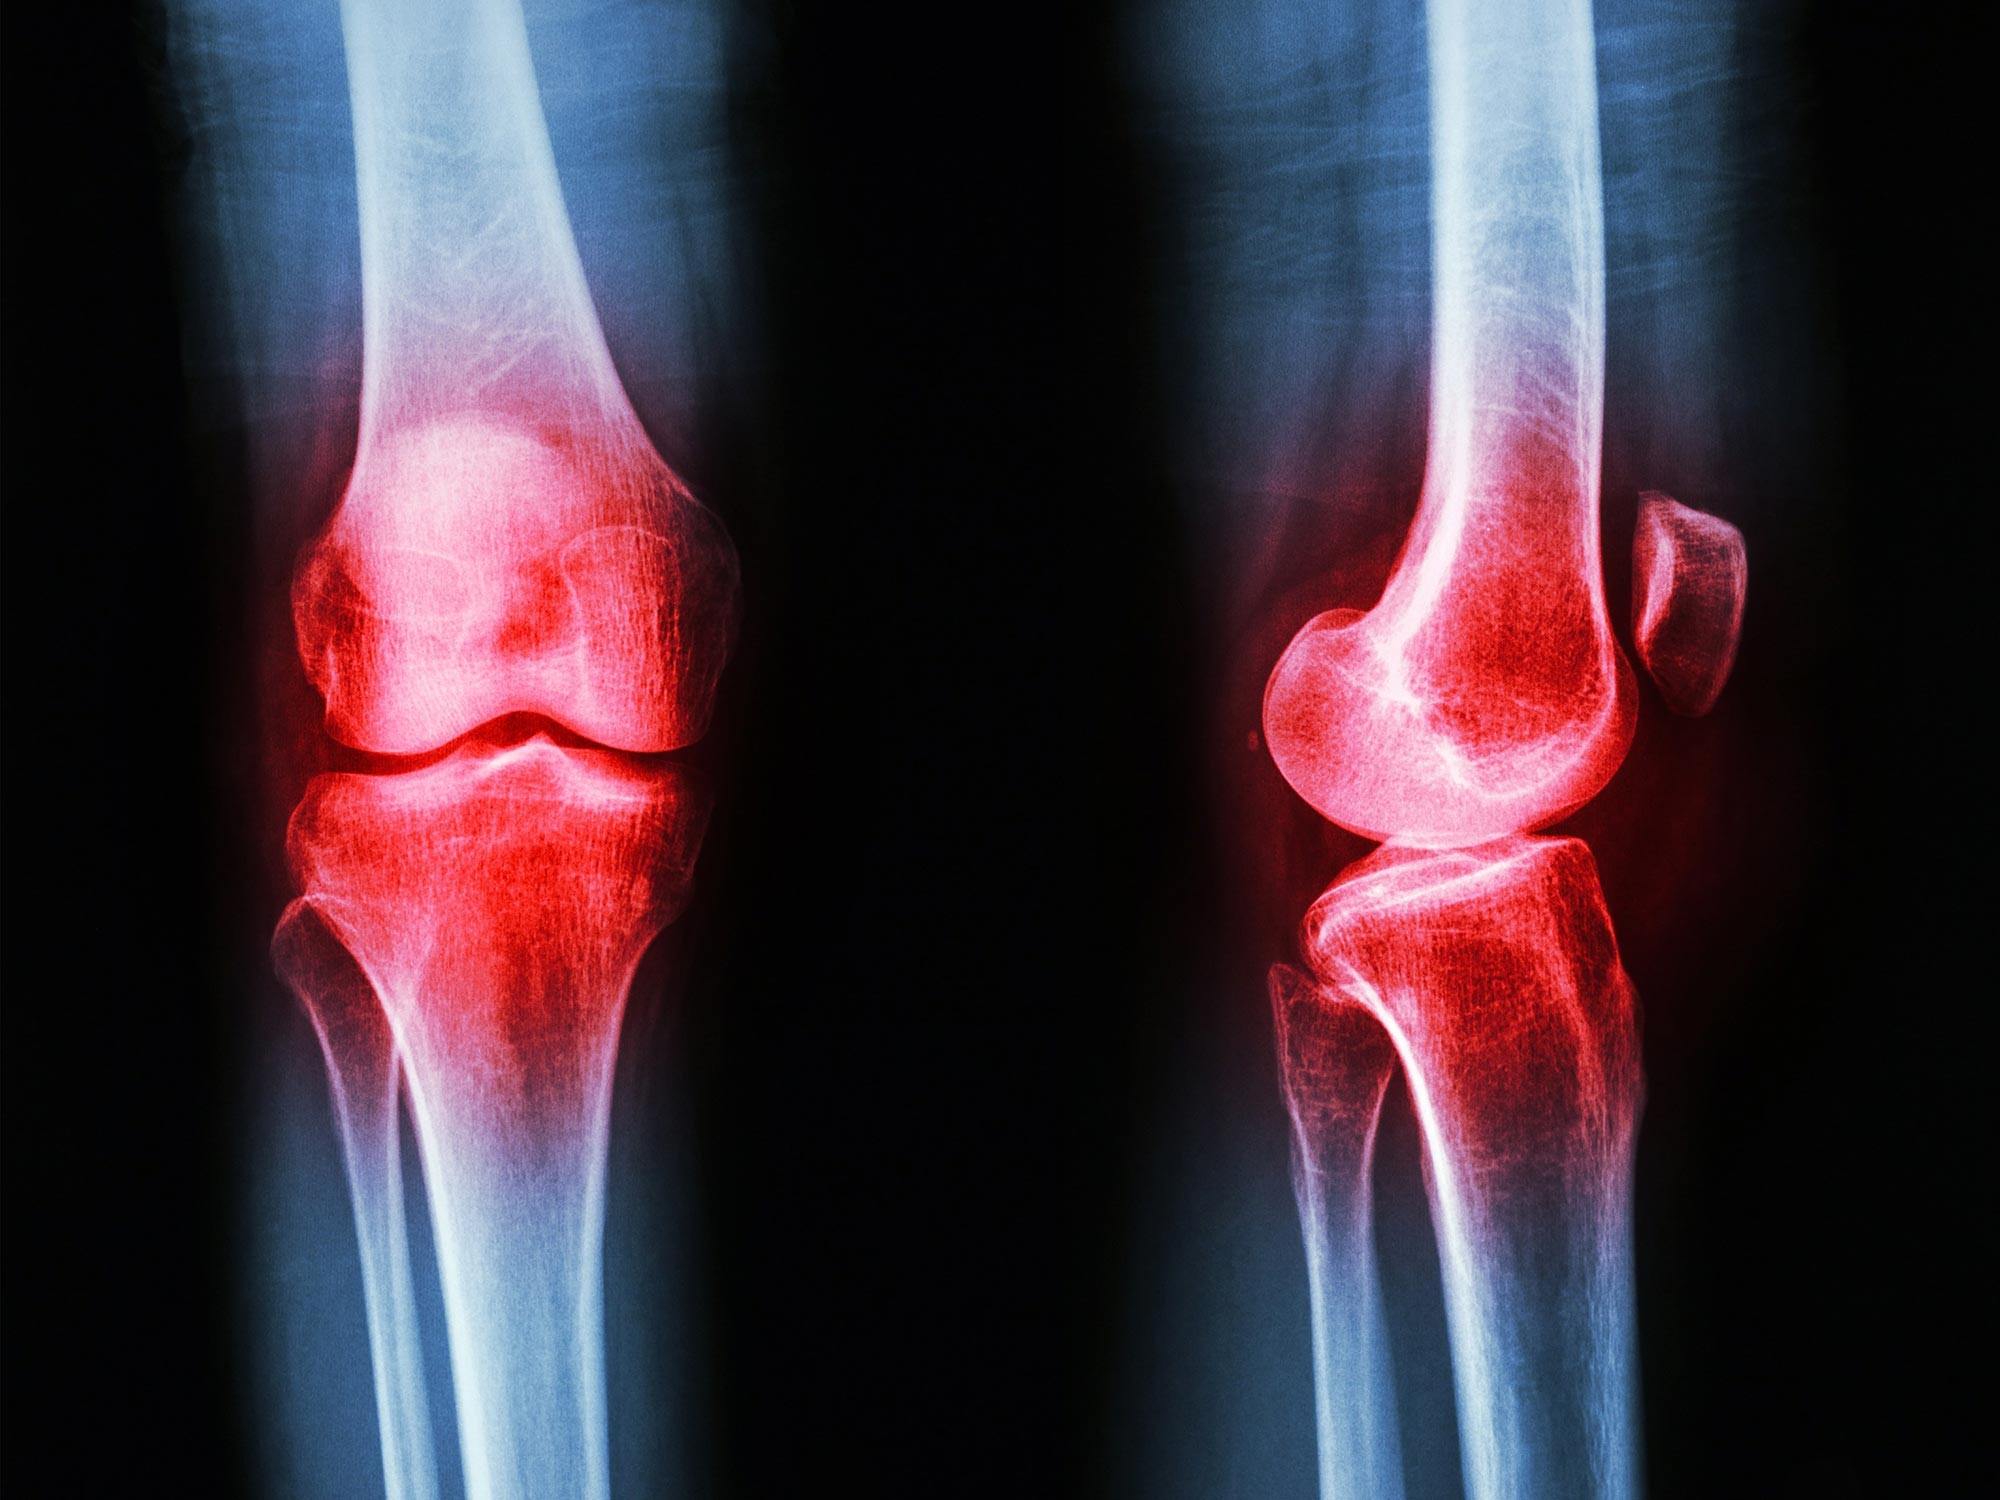

Nedávná studie publikovaná v časopise Engineering identifikovala slibný nový terapeutický cíl pro léčbu revmatoidní artritidy (RA). Vědci zjistili, že přírodní sloučenina, obakulakton (OL), může zmírnit onemocnění nikoli plošným potlačením imunitního systému, ale nápravou metabolické nerovnováhy ve způsobu, jakým tělo zpracovává tuk.

Revmatoidní artritida postihuje přibližně 1 % světové populace, což představuje miliony lidí, kteří čelí chronické bolesti a potenciální invaliditě. Současná terapie často neposkytuje úplnou remisi nebo je doprovázena závažnými vedlejšími účinky.